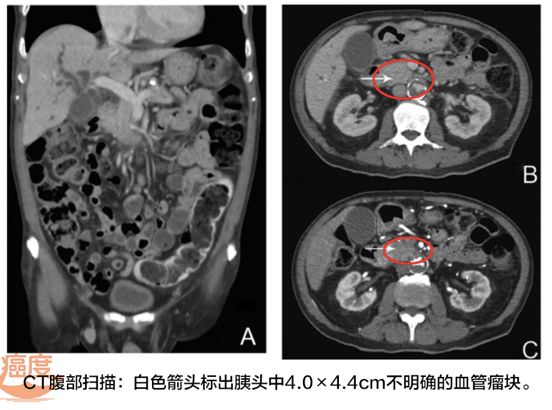

2015年1月,一名77岁的男士因为持续2周的黄疸而入院,病人还有瘙痒、淤伤、茶色尿等症状,食欲不振,一年体重下降了13公斤。腹部和骨盆的CT扫描显示肝内胆管和胆总管显著扩张,胰腺头部有个4×4.4厘米的肿块。根据临床表现和影像学检查结果,多学科会诊的专家共识认为是可以切除的胰头腺癌。